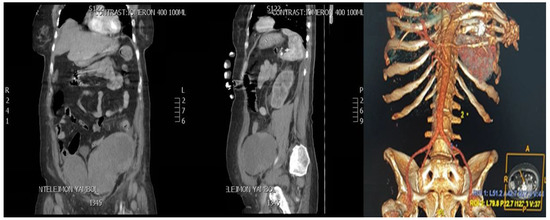

2.3. CT Scan Report